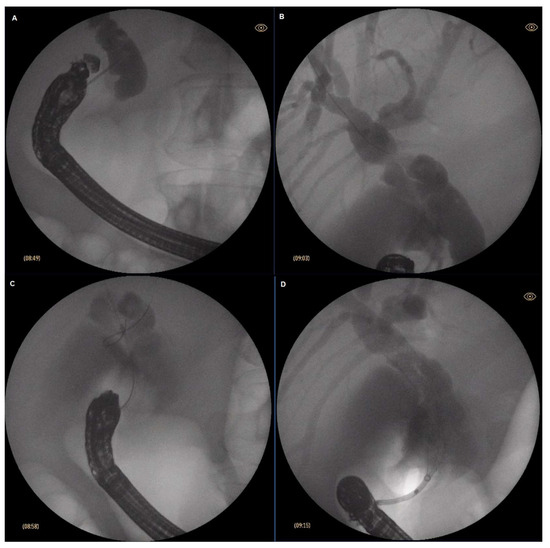

A curvilinear echoendoscope (Olympus GF-UCT180, Olympus, Hamburg Germany) was introduced then and placed at the first part of the duodenum. Insufflation with CO2 was utilized instead of ambient air (Olympus UCR, Hamburg, Germany). Once in the bulbar part of the duodenum, the common bile duct was identified endosonographically. Color Doppler was used to delineate the surrounding vascular structures and to exclude the presence of major interposing vessels. A crucial step was to ensure that the endoscope was in such a position so that the needle would be oriented towards the liver hilum. This was achieved by further adjusting the position of the endoscope using fluoroscoping guidance (Philips BV Pulsera C-arm, Philips, Best, The Netherlands). Generally, if on fluoroscopy the endoscope was in a long position and with the tip pointing upwards and facing the insertion tube, it was considered the optimal position to access the common bile duct. A 19Ga fine needle aspiration (FNA) needle (ExpectTM needle; Boston Scientific; Marlborough, MA, USA) was used to puncture the common bile duct. To verify the correct position, bile was initially aspirated, followed by contrast injection (Iopamidol 370 mg/mL) to obtain cholangiogram. Slight irrigation with saline was then performed, followed by insertion of 0.025 inch guidewire (JagWire RevolutionTM; Boston Scientific; Marlborough, MA, USA), which was then placed in as deep as possible in the intrahepatic bile ducts. Slight withdrawal of the needle was used to avoid “sheering” in case of advancement of the guidewire in the correct direction was cumbersome. Once stable position of the guidewire was achieved, dilation of the fistulous tract was performed using a cystotome (10fr in 1 case, 6fr in 6 cases; Endo-flex GmbH, Voerde, Germany) paired with electrosurgical unit ERBE Vio 300D (Erbe Elektromedicin Gmbh, Tübingen, Germany) set at Endocut I (effect 2, cut duration 3, cut interval 3). Eventually, FC-SEMS (WallFlexTM; Boston Scientific; Marlborough, MA, USA) was inserted—60/10 mm in six cases and 80/10 mm in one case. Every effort was made to place the stent just below the confluence to avoid inadvertent segmental obstruction of the intrahepatic bile ducts. An SEMS was intended to extend about 3 cm in the duodenum to reduce the risk of stent migration. After successful positioning of the stent, endoscopic and fluoroscopic evaluation were performed to verify the presence of bile flow and evacuation of contrast media from the bile ducts and to exclude hemorrhage. The described steps of EUS-CDS are depicted in Figure 1.

Figure 1. Steps of EUS-CDS: (A) Puncture of the common bile duct; (B) guidewire insertion towards the hilum; (C) tract dilation with a 6fr cystotome; (D) stent insertion.